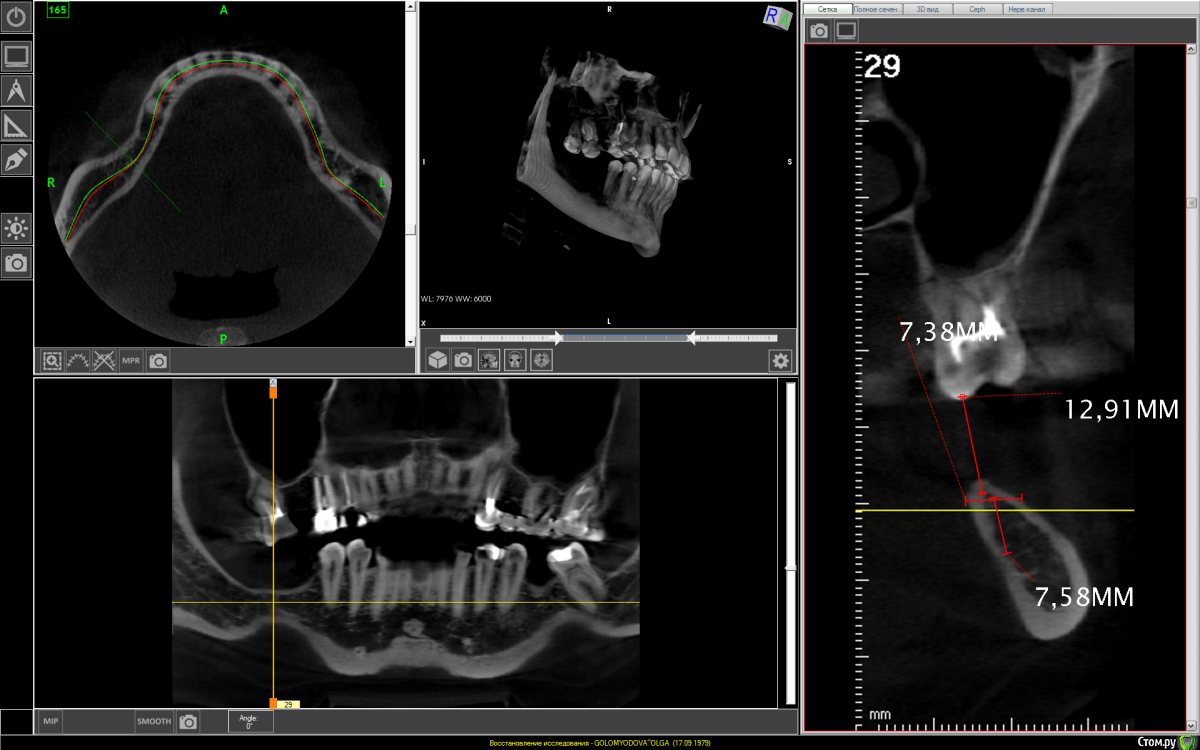

It'sGeorgy Опубликовано 26 февраля, 2021 Поделиться Опубликовано 26 февраля, 2021 1. Нет никакого смысла заниматься низом справа, если вы не будете заниматься верхом справа.2. Ситуация непростая, но я за имплантаты 8мм. + 6мм. с полированной шейкой. Посмотрим, что другие здешние коллеги еще подскажут. 2 Ссылка на комментарий

It'sGeorgy Опубликовано 27 февраля, 2021 Поделиться Опубликовано 27 февраля, 2021 (изменено) Спасибо за мнение!Значит можно без костной пластики обойтись?Если бы вы были моей пациенткой - я бы не стал вам рекомендовать зи проводить костную пластику. В плане ширины кости особых проблем у вас нет. Есть серьезная проблема в недостатке высоты костной ткани. Вертикальная костная пластика, точнее, ее отдаленные результаты - вопрос дискуссионный. Есть исследования, подтверждающие невысокую выживаемость результатов вертикальной пластики, но так же есть и доктора, которые демонстрируют хорошие и стабильные результаты. Здесь я на стороне первых.Но и здесь нужно понимать, что есть определенные риски: коронки на имплантатах будут в почти два раза больше в высоту, чем сами имплантаты. Есть мнения, что это плохо и создаётся рычаг. Резюмируя повторюсь: выбирая из этих двух рисков, я бы выбрал вариант с одним имплантатом 8мм и одним коротким 6мм с полированными шейками.Само собой, что установку таких имплантатов я бы проводил только по шаблону. И такая операция была бы возможно только при полной реабилитации жевательной эффективности: надо так же работать сверху справа и снизу слева. Изменено 27 февраля, 2021 пользователем It'sGeorgy 1 Ссылка на комментарий